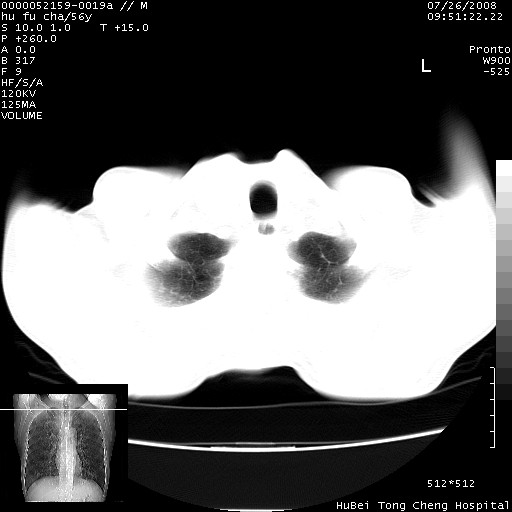

以下是引用zsl6918在2008-8-25 22:47:00的发言:[br]胸骨,胸椎及肋骨均可见多发转移表现,肝内低密度结节不除外转移。原发灶可能在右肺。双侧可见支扩表现。

以下是引用卜一在2008-8-26 8:02:00的发言:[br][br] 支持:肺癌并肺内,胸骨,胁骨,胸椎及肝内转移!另:左肺支气管扩张征伴感染! [br]